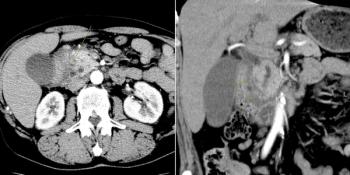

A 50-year-old man undergoes CT examination for workup of hematuria and abdominal pain. Noncontrast and postcontrast images from the CT are shown. What is your diagnosis?